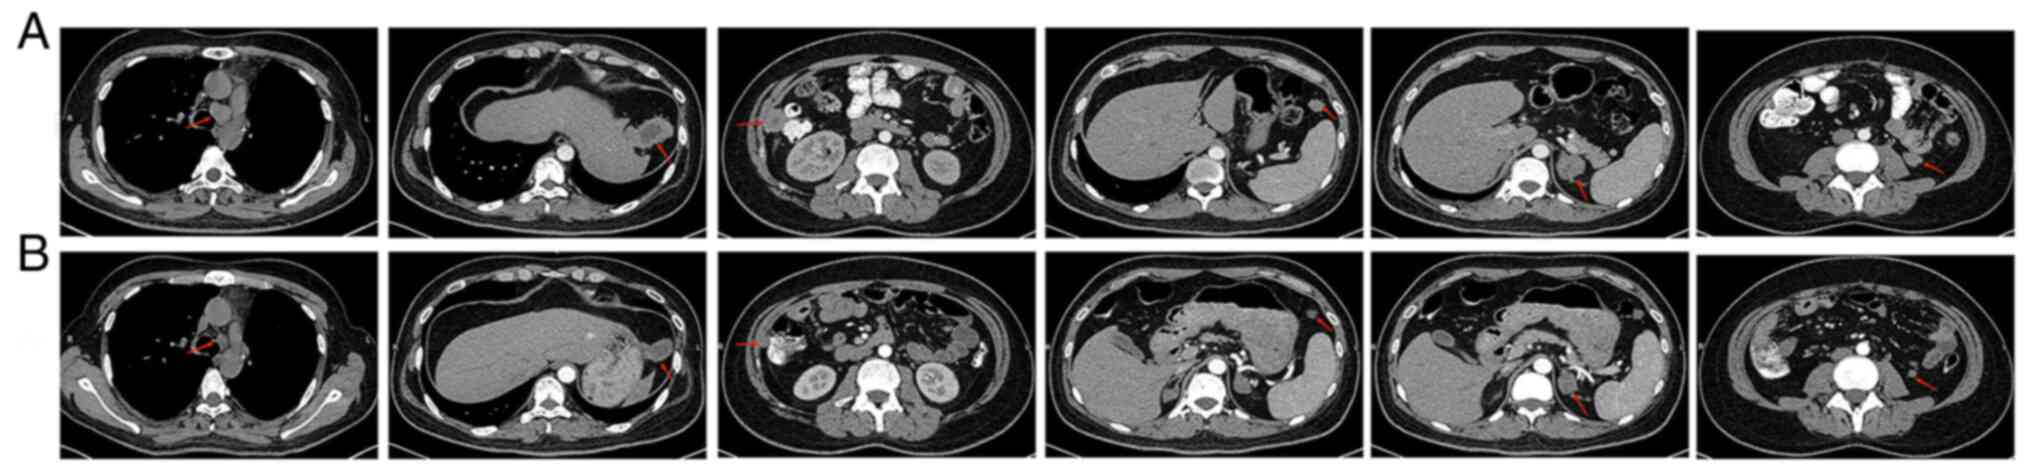

After four months, the patient returned, presenting with cough and back pain. Hematologic examination revealed that the number of white blood cells (WBC) was increased to 14.68×109/l [normal range (NR), 4.0-10.0 ×109/l], accompanied with a platelet count of 517×109/l (NR, 100–300×109/l), without any chills or fever. After five months, the patient returned to the hospital and CT examination revealed enlarged lymph nodes in the mediastinum and a small amount of fluid in the right pleural cavity. Multiple metastases were found in the abdominal cavity, the largest of which was located in the lateral left lobe of the liver (~5.7×3.0×4.0 cm in size), markedly enlarged adrenal glands bilaterally (~2.7 cm) and soft tissue lesions below the left kidney, anterior to the spleen and in the right paracolic sulcus, ~1.8, 1.5 and 2.9 cm in diameter, respectively (Fig. 5). A CT-guided percutaneous biopsy of the lesion on the right paracolonic sulcus was performed and subsequent IHC indicated a malignancy of mesenchymal origin; it was considered a possible metastasis of the sarcomatoid component. After a full discussion, the therapeutic plan was changed to a combination of targeted therapy with immunotherapy (Alectinib + Anlotinib + Tirelizumab). Before the treatment started, informed consent was obtained from the patient and the patient's family. The patient began treatment with Anlotinib (12 mg, qd, d1-14, q21d) and with Tirelizumab (200 mg, q21d). After the first treatment cycle, the patient experienced a significant improvement in his cough and complaints of pain. Furthermore, the patient's WBC and platelet counts decreased to normal and the right retroauricular mass had disappeared. A repeat CT after the second treatment cycle revealed a significant reduction in the pleural effusion of the right lung and in the size of the mediastinal lymph nodes, and the lesions in the abdominal cavity (largest lesion was ~3.2×2.0×2.3 cm); furthermore, the lesions in the lower left kidney, the anterior spleen and the right paracolic sulcus were reduced to ~1.0, 1.1 and 1.2 cm in diameter, respectively (Fig. 5). The tumor response to treatments was evaluated according to the New Response Evaluation Criteria In Solid Tumours: Revised RECIST Guideline (version 1.1) (8). The sum of the diameters of the target lesions was reduced by >30%, taking as reference the baseline sum diameter. These observations resulted in the rating as partial response (PR) for the disease. The patient tolerated the combined treatment (Alectinib + Anlotinib + Tirelizumab) well, only experiencing mild diarrhea over 7 months on the regimen; currently, the patient remains on this treatment plan.